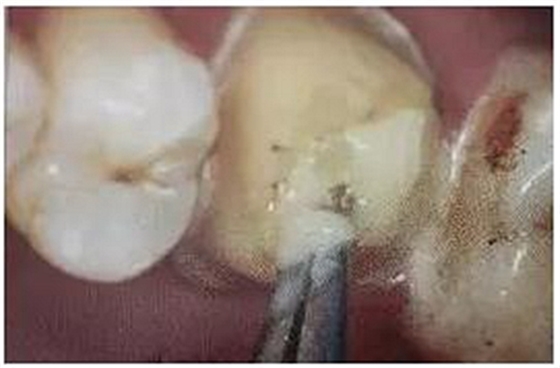

8. 酸蝕和根管內(nèi)酸蝕劑的去除

使用全酸蝕粘接系統(tǒng)粘接纖維樁時(shí),用磷酸凝膠對根管進(jìn)行酸蝕處理,然后再徹底沖洗干凈,根管內(nèi)酸蝕劑殘留的發(fā)生容易被忽視,這也是影響纖維樁粘接的重要因素之一。

單純的使用三用槍即使反復(fù)沖洗液難將根管內(nèi)的酸蝕劑沖洗盡,尤其是后牙根管。

(冠部及根管全酸蝕)

(三用槍沖洗)

(注射器沖洗)

(根管毛刷清洗)

臨床建議用注射器、三用槍和柱狀毛刷,三者聯(lián)合反復(fù)沖洗。如再配合超聲波振蕩沖洗更佳。